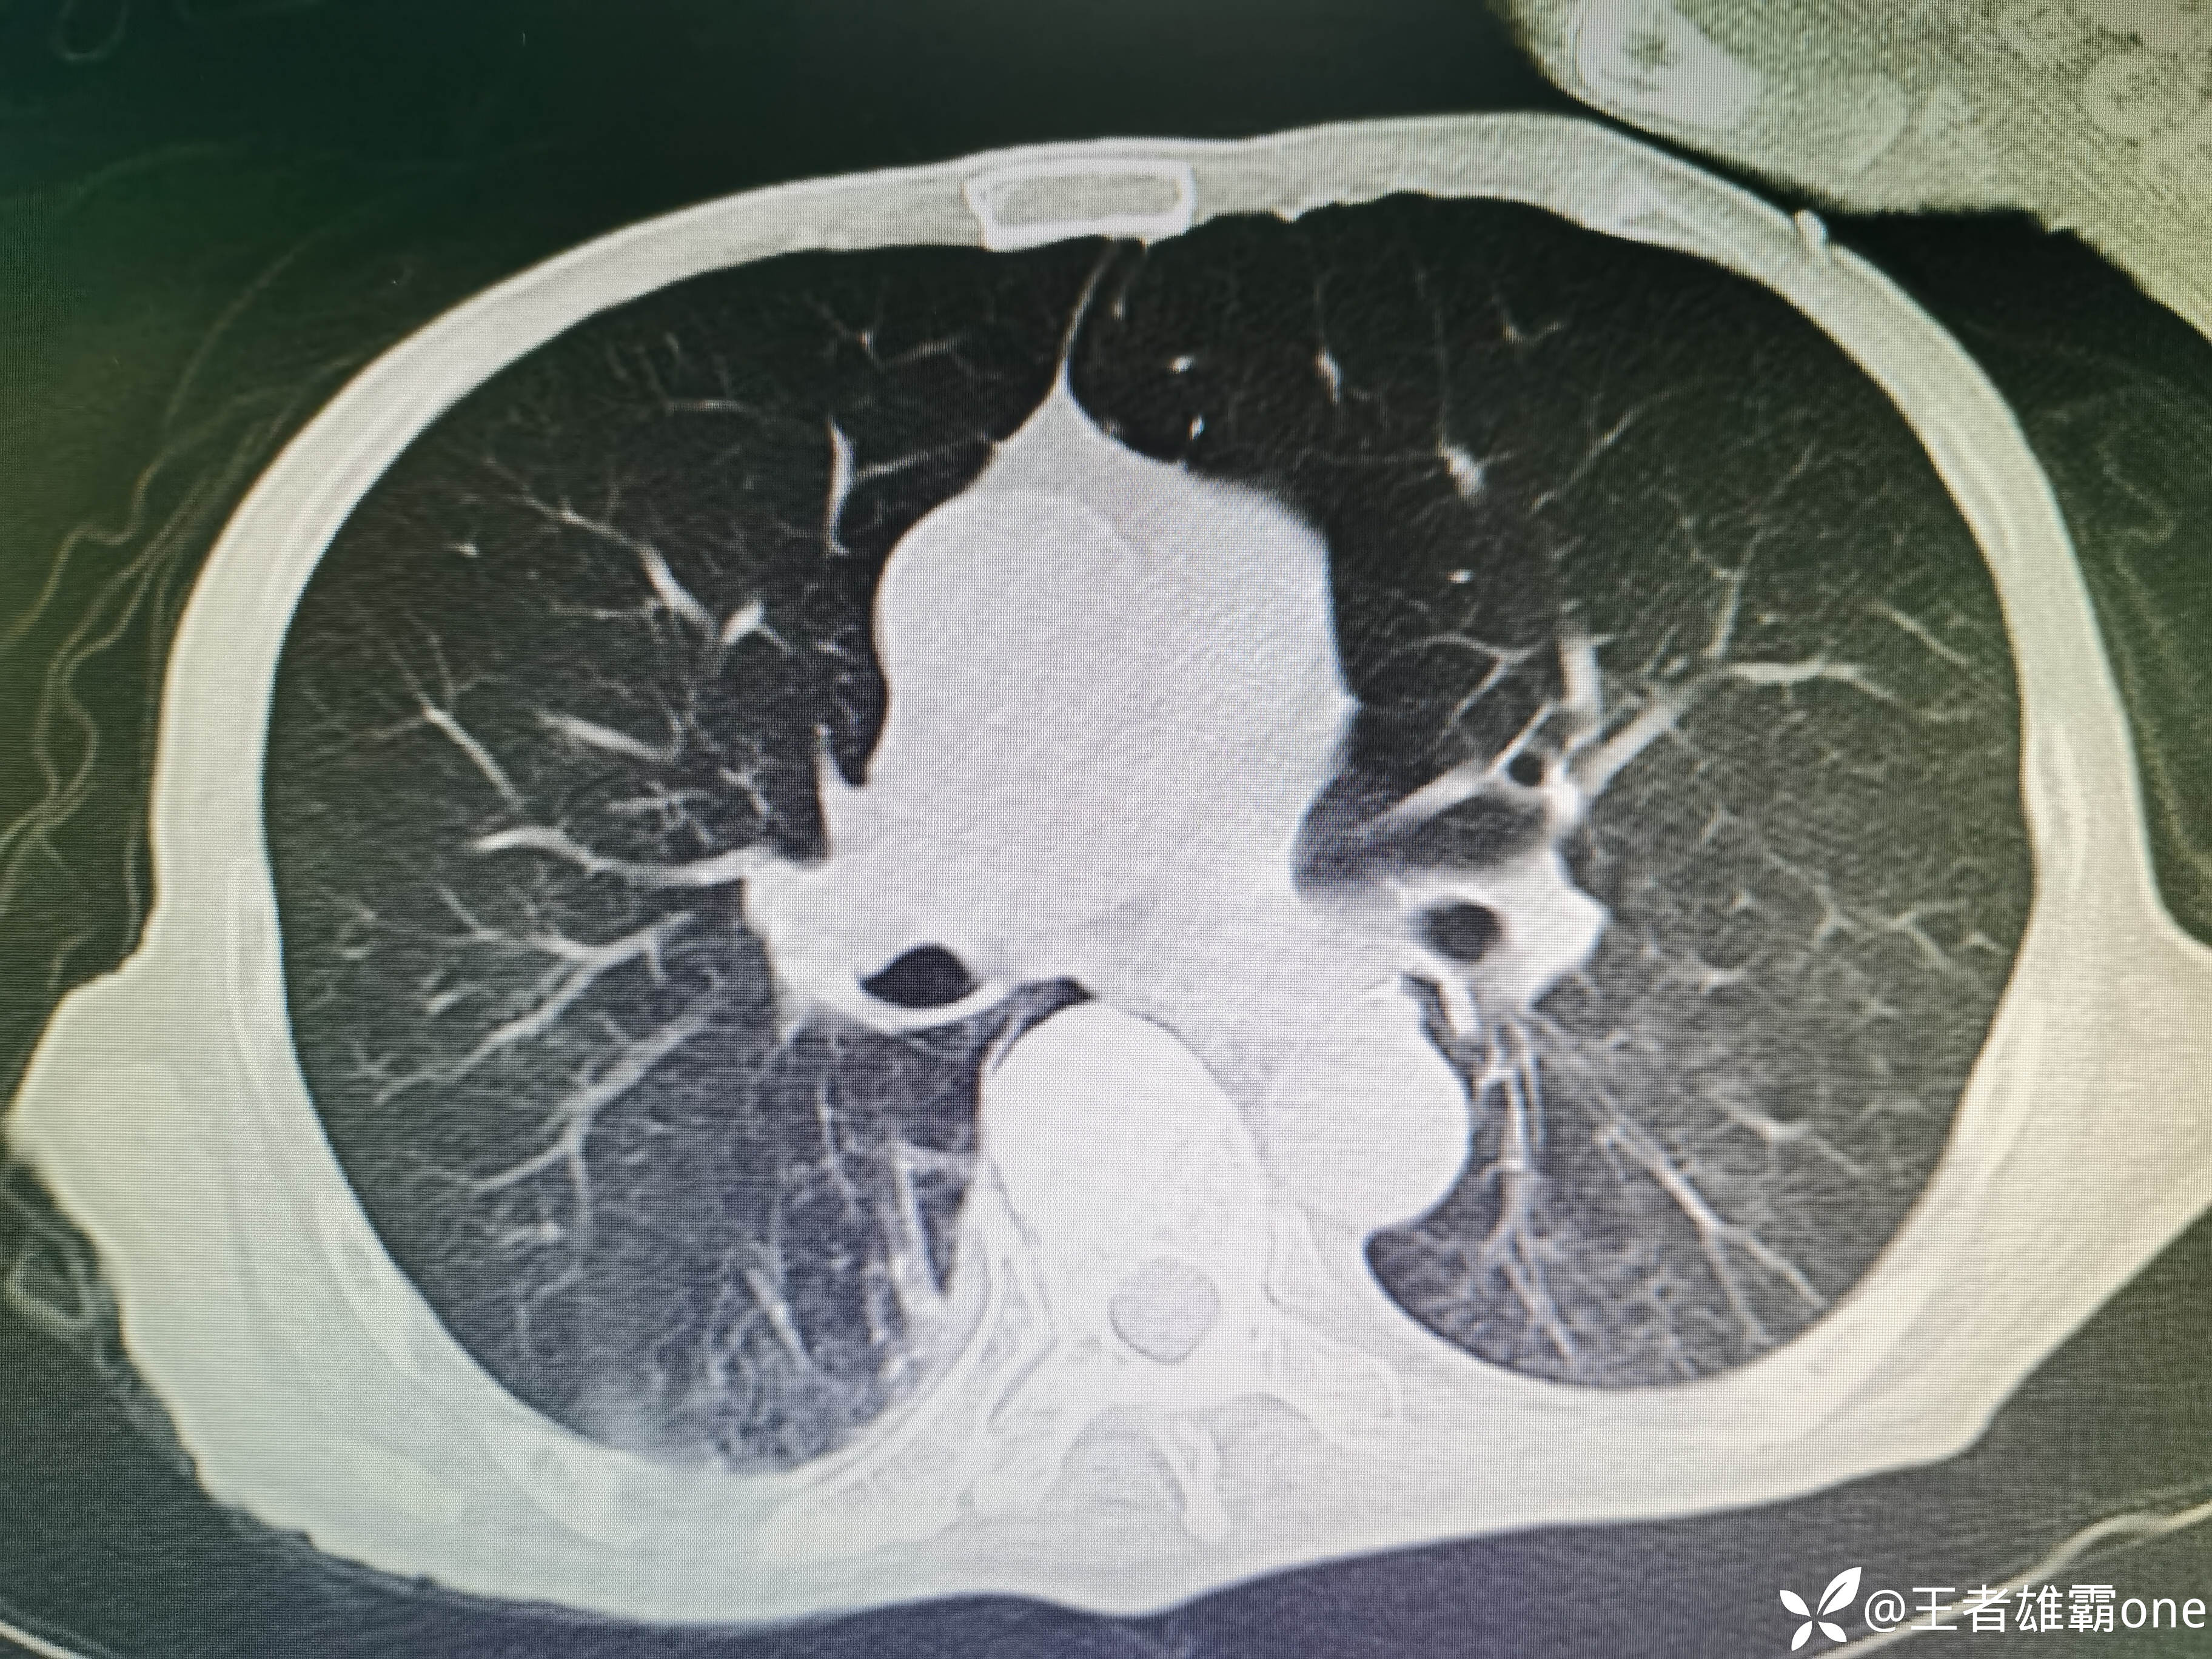

入院时胸部CT:

具体图片: